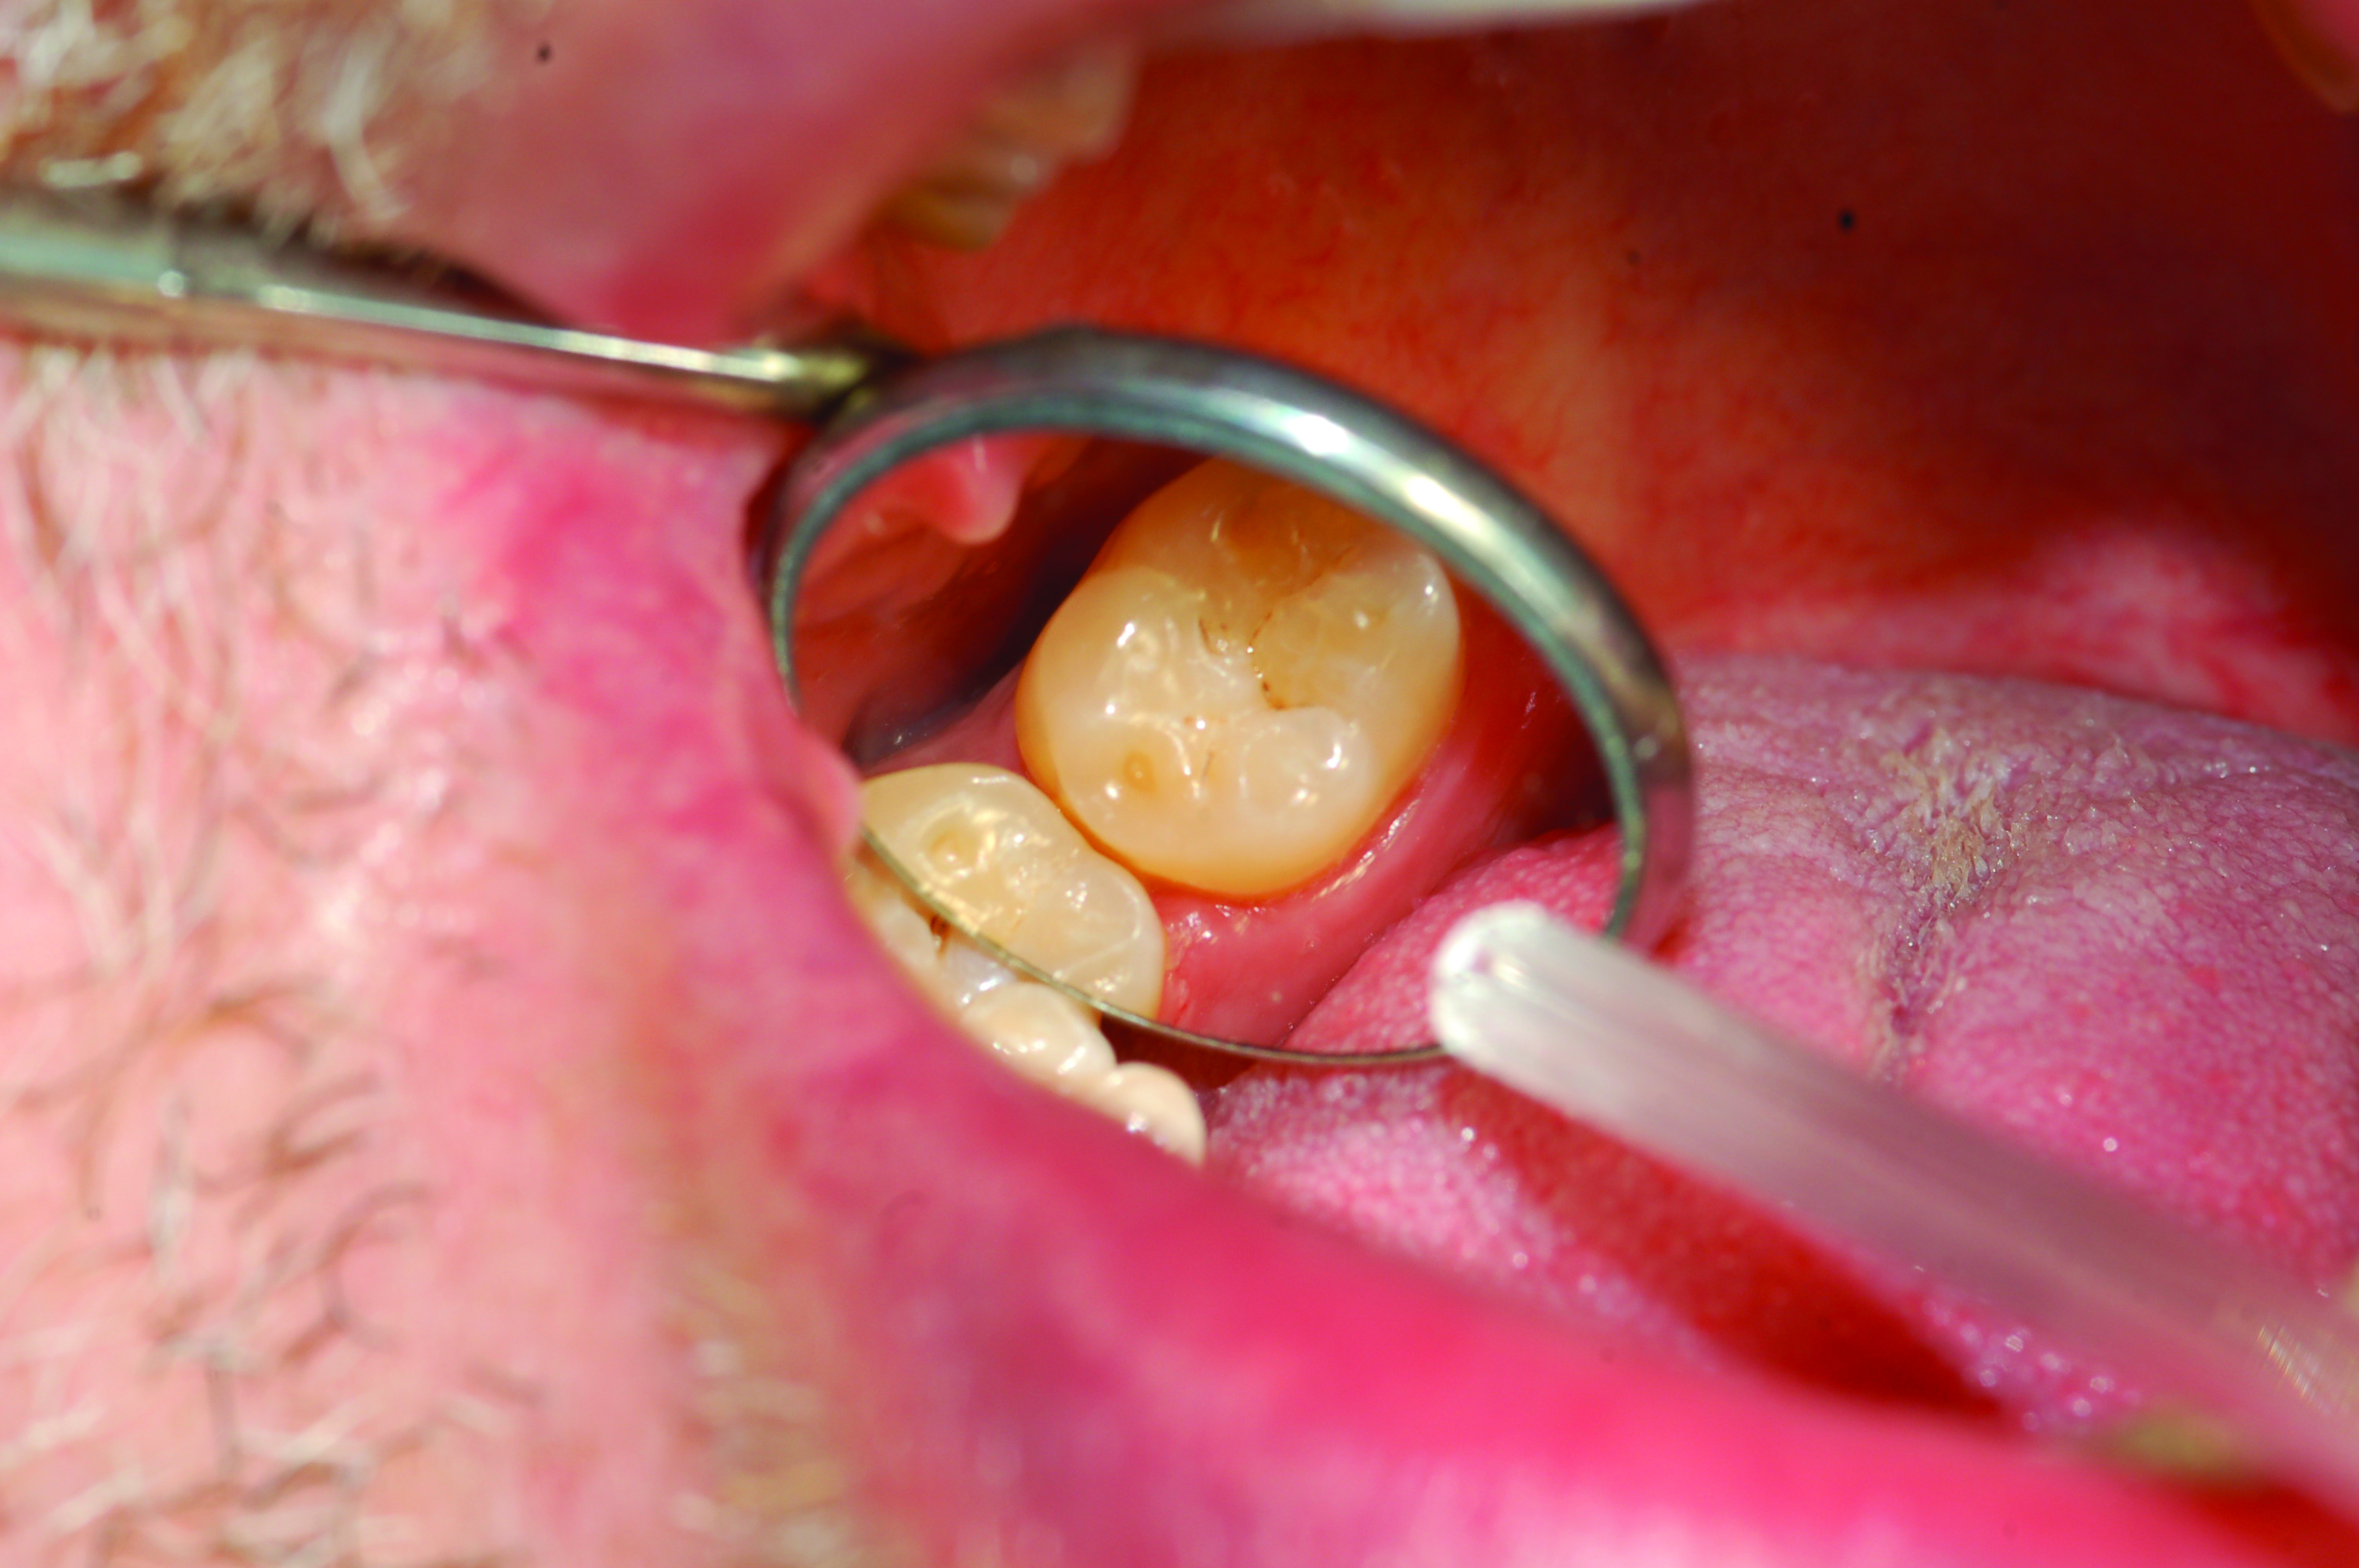

Accurate impressions of the upper and lower dentition are required for custom fabrication of a MAD. Because some appliances extend beyond the teeth, it is recommended that the impression capture at least 3-4 mm of soft tissue surrounding the teeth. The lower impression must capture the distal surfaces of the most distal teeth on both sides of the arch. The MAD must be fabricated to extend to include these surfaces; otherwise, diastemas may form with the adjacent mandibular teeth (Figure 2 through Figure 4).

Fig 2. Inadequate posterior extension of a MAD. The posterior extent of the MAD failed to capture the distal surfaces of the mandibular second molars. All third molars were absent.

Fig 3. Eight months later, diastemas had developed between the mandibular second and first molars.

Fig 2. Inadequate posterior extension of a MAD. The posterior extent of the MAD failed to capture the distal surfaces of the mandibular second molars. All third molars are absent.

Fig 3. Eight months later, diastemas have developed between the mandibular second and first molars.